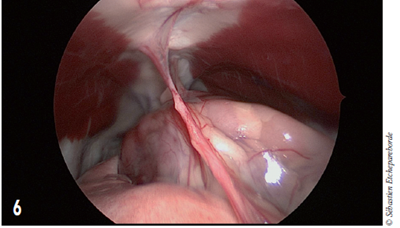

Photo 6 - Vue thoracoscopique

L’animal est sur le dos.

On distingue du poumon sur la gauche.

Du sternum (en haut) par le médiastin cranial dans lequel se situe la masse